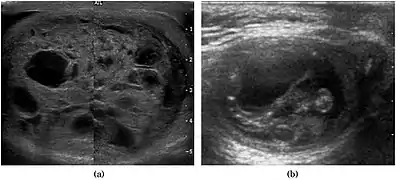

Fig. 3. Seminoma. (a) Seminoma usually presents as a homogeneous hypoechoic nodule confined within the tunica albuginea. (b) Sonography shows a large heterogeneous mass occupying nearly the whole testis but still confined within the tunica albuginea, it is rare for seminoma to invade to peritesticular structures.

Approximately 95% of malignant testicular tumors are germ cell tumors, of which seminoma is the most common. It accounts for 35%–50% of all germ cell tumors. Seminomas occur in a slightly older age group when compared with other nonseminomatous tumor, with a peak incidence in the forth and fifth decades. They are less aggressive than other testicular tumors and usually confined within the tunica albuginea at presentation. Seminomas are associated with the best prognosis of the germ cell tumors because of their high sensitivity to radiation and chemotherapy.

Seminoma is the most common tumor type in cryptorchid testes. The risk of developing a seminoma is increased in patients with cryptorchidism, even after orchiopexy. There is an increased incidence of malignancy developing in the contralateral testis too, hence sonography is sometimes used to screen for an occult tumor in the remaining testis. On US images, seminomas are generally uniformly hypoechoic, larger tumors may be more heterogeneous [Fig. 3]. Seminomas are usually confined by the tunica albuginea and rarely extend to peritesticular structures. Lymphatic spread to retroperitoneal lymph nodes and hematogenous metastases to lung, brain, or both are evident in about 25% of patients at the time of presentation.